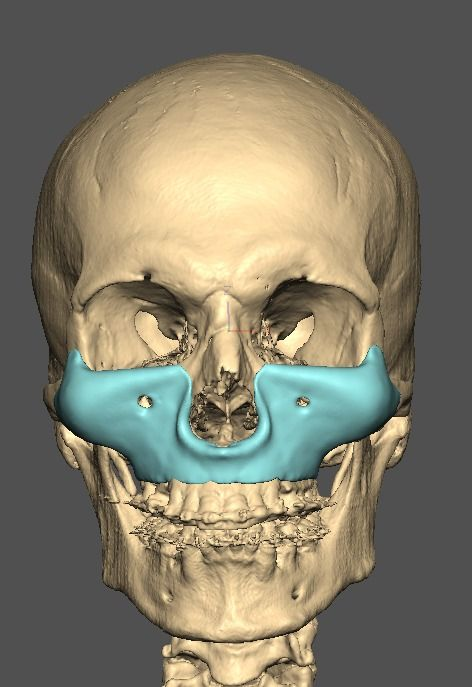

I know a guy who designed this for himself in collaboration with an asian implant company.

Not the final product yet, he is making adjustments as we speak.

Found a surgeon willing to insert it.

Giant and Eppley were the inspiration